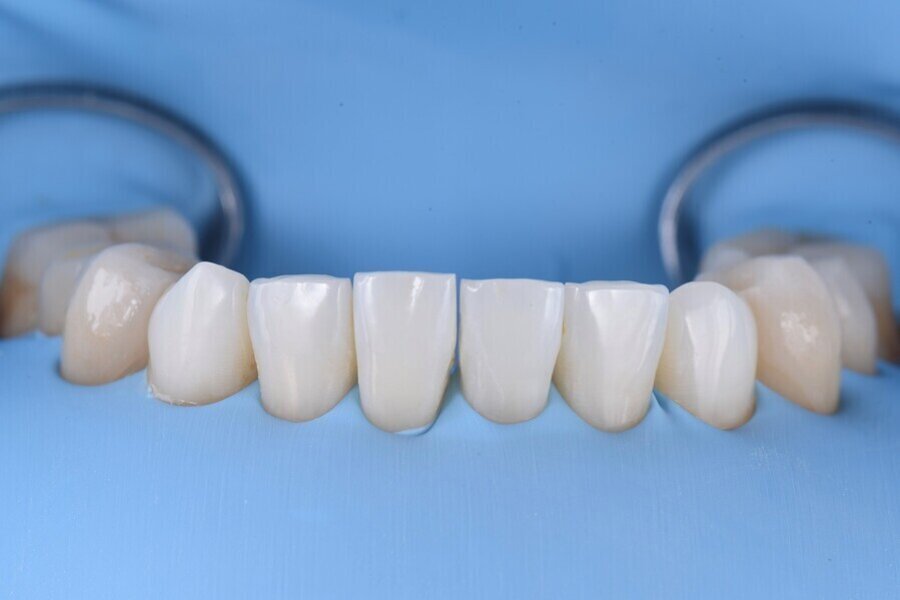

Následně byl zhotoven digitální wax-up ve frontálním úseku horní čelisti, aby bylo možno ověřit estetiku plánované rekonstrukce a vést minimálně invazivní preparaci zubů na základě zhotoveného mock-upu (obr. 8). Finální preparace (obr. 9) se z větší části omezila na interproximální oblasti (obr. 10). Poté byl proveden finální digitální otisk při aplikaci retrakční niti. (obr. 11).

V rámci digitálního designu navržené rekonstrukce byla provedena částečná redukce dolní poloviny bukální plochy plánovaných korunkových náhrad, aby bylo umožněno vrstvení keramiky pro dosažení co nejlepšího estetického výsledku (obr. 12 a 13).

Obr. 13: Konečná rekonstrukce (s prostorem pro frontální stratifikaci).

Obr. 14a, b: Finální náhrady.